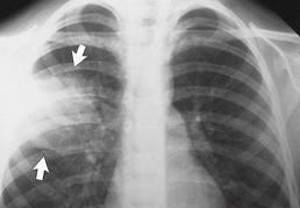

Незаменимым для постановки точного диагноза пневмонии является рентгенография грудной клетки. Она проводится в прямой, а при необходимости и в боковой проекции и позволяет не только установить диагноз острой пневмонии и выявить возможные осложнения, но и оценить эффективность лечения.

- Лучевая диагностика. Чтобы определить воспаление легких у взрослых, проводится такое обследование, как рентгеноскопия. Считается, что его результаты являются основополагающими в постановке диагноза, поскольку на снимке хорошо видно зону воспалительного процесса. Назначаться может и компьютерная томография легких.